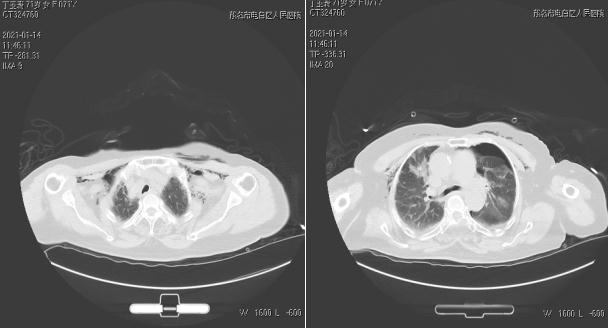

患者于20:55由120送入全科醫(yī)學(xué)科,經(jīng)過詢問病史,患者于3天無明顯誘因出現(xiàn)咳嗽、咳痰,少量黃白痰,難咳出,伴氣促,當(dāng)?shù)刂委煱Y狀無好轉(zhuǎn),1小時前出現(xiàn)氣促明顯加重,呼吸困難明顯,不能平臥,伴煩躁不安。胸片檢查提示:雙側(cè)氣胸。入院時煩躁不安,表情痛苦,口唇發(fā)紺,桶狀胸,雙上肺叩診鼓音,聽診呼吸音消失,雙下肺呼吸音粗,可聞及哮鳴音。梁志朋副主任醫(yī)師立刻給予患者高流量吸氧、平喘等處理,急查血氣分析等,并向李文峰匯報相關(guān)情況。為進一步了解肺部情況,CT檢查提示雙側(cè)氣胸(左側(cè)壓縮約70%,右側(cè)壓縮約60%),情況緊急,梁志朋副主任醫(yī)師立刻給予病人左側(cè)胸腔閉式引流術(shù),過程順利,患者氣促癥狀好轉(zhuǎn),血氧飽和度上升到92%左右。

術(shù)前CT